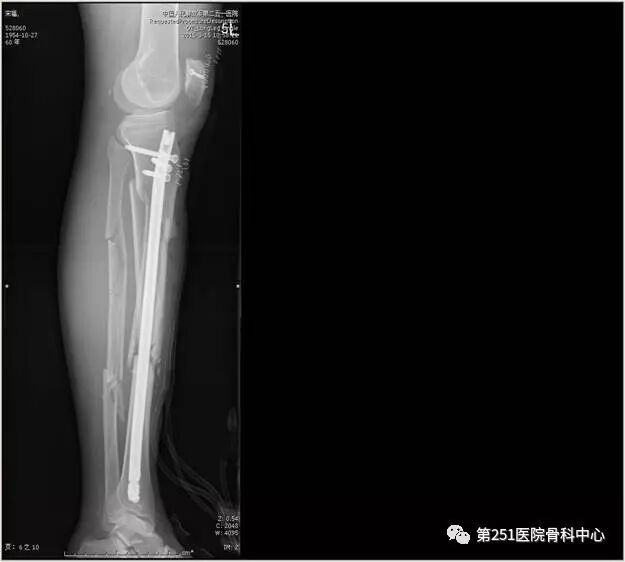

病例5:男性,64岁,车祸伤,胫腓骨中上段粉碎性骨折 。

![]()